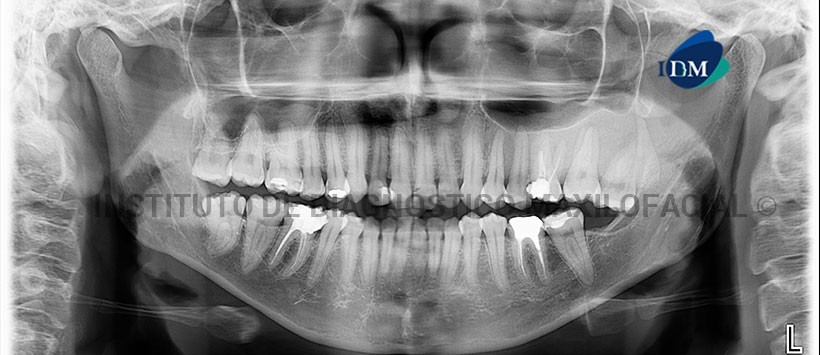

En la radiografía panorámica (Figura 1) imagen radiopaca de densidad ósea de limites no definidos que se extiende de la región de pieza 25 hasta la región de la tuberosidad y en sentido cefálico-caudal del reborde alveolar hasta el piso del seno maxilar. La lesión ocasiona desplazamiento de la cima del reborde alveolar así como del piso del seno maxilar, se aprecia un aumento de volumen de la región de la tuberosidad y la mimetización de la lámina dura de las piezas comprometidas.